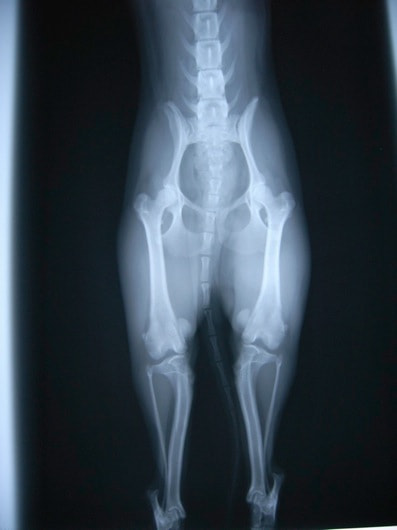

■ 症例22 ポメラニアン 1歳5か月 去勢雄

左後肢の挙上を主訴に来院した。整形学的検査、レントゲン検査より左右の膝蓋骨脱臼(左GradeⅡ〜Ⅲ、右Grade Ⅱ)を認めた。また、脛骨の前方引き出し試験の際に、引き出し兆候は認められないものの、疼痛が認められたため、前十字靭帯の損傷が疑われた。術中における、目視および関節内の操作によって、前十字靭帯の損傷や過伸展といった異常が認められなかったため、膝蓋骨脱臼の整復のみ実施した。手術手技は縫工筋及び内側広筋の解放、脛骨粗面の外側転位、滑車ブロック形造溝術、内外側関節包の縫縮を実施した。本症例は跛行もなく経過良好である。しかし、頸骨高平部の角度(TPA)が 右26.2°、左24.9°であり、解剖学的に前十字靭帯損傷のリスクが高いことから今後の経過に注意が必要である。